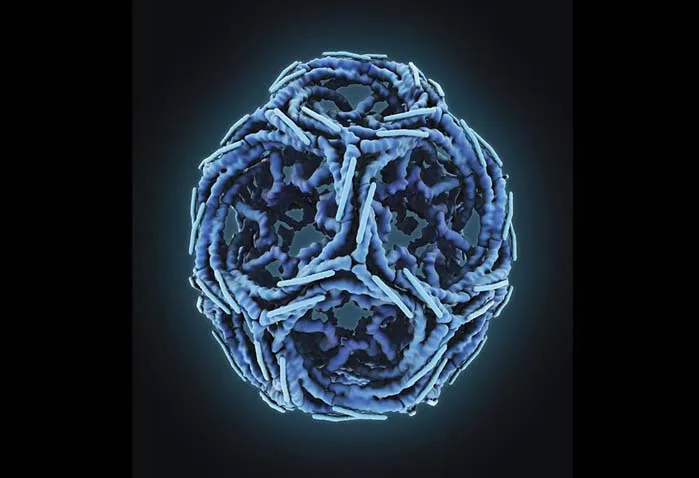

ویروس ابولا

این طراحی، ساختار درونی یک ویروس ابولا را نشان میدهد. هستهی مرکزی هم به شکل سه بعدی نشان داده شده تا ساختار درونی بیشتر مشخص باشد.

پهنای ویروس ابولا حدودا ۱۰۰ نانومتر (۰٫۰۰۰۱ میلیمتر) است؛ این یعنی تقریبا ۲۰۰ برابر کوچکتر از اکثر سلولهایی که آنها را آلوده میکند.

طراح این تصویر از رنگهای ملایم استفاده کرده تا عناصر مختلف این ویروس کوچک و مرگبار را نشان دهد. این تصویر نشان میدهد که با طراحی میتوانیم جزییات زیادی را را در سطوح مختلف با زیبایی و وضوح بالایی به تصویر بکشیم.